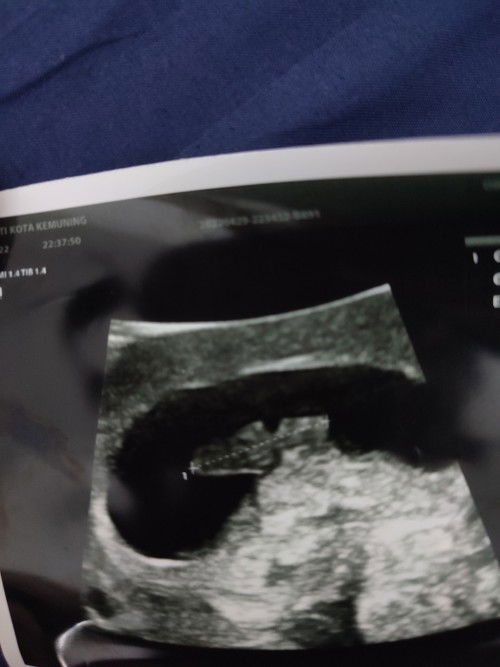

Hi. Sy nk tanya, normal ke kalau bentuk kantung macam ni? Sy baru dlm 8 weeks #ingintahu #firstbaby #bantusharing #firstmom

normal sis, kantung macam macam bentuk, janji nampak fetal tu, Insyallah baik baik sja ya sis.